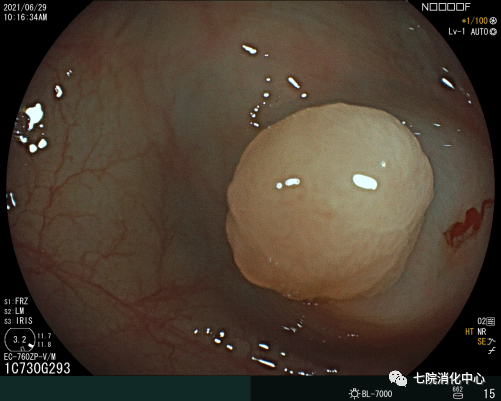

常用于切除无蒂息肉,通过注射缓冲液到黏膜下层的空间,使上皮与底层组织分开,使病变分离。包括整块切除和分次切除,目前黏膜下注射切除法是最常用的一种EMR切除法,其他EMR切除方法还有透明帽辅助EMR、注水法/水下法EMR等,EMR在实现大肠息肉的完整内窥镜切除术方面明显优于冷圈套器,但它需要黏膜下注射和电灼,因此不可避免出现延迟出血、息肉切除术后综合征和穿孔等并发症。

ESD相对于EMR而言,可最大限度地减少肿物的残留和复发。ESD通常应用>20mm、非颗粒样侧向发育病变。ESD相对于传统的分片黏膜切除术来说是一种复发率低、可获得更好的病理标本的技术。ESD的不足是穿孔率高、过程耗时。多项研究表明,ESD穿孔率约5%。大量研究报告了ESD的临床结果,整块切除的疗效好以及大型浅表结直肠肿瘤的长期低复发率。